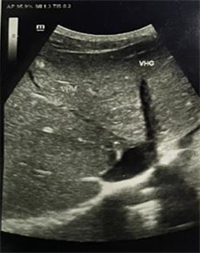

Abdominal ultrasonography showed a homogenous dysmorphic hepatomegaly with a hypertrophic caudate lobe, a splenomegaly and a mild ascites (Figure 1). Right and middle hepatic veins were obstructed. The left hepatic vein was permeable and dilated (Figure 2). We completed imaging with an abdominal computed tomodensitometry (Figure 3) with contrast enhancement. We observed the same aspect of hepatomegaly with an enlarged caudate lobe, splenomegaly and mild ascites. Moreover, the right hepatic vein was hyperechoic suggesting an obstructive thrombosis. The middle hepatic vein was also hyperechoic and partially obstructed. The left hepatic vein and the inferior vena cava were normal. These

Figure 2. Abdominal ultrasonography of November 2022 showing the obstruction of the right and middle hepatic vein with a permeable and dilated left hepatic vein.